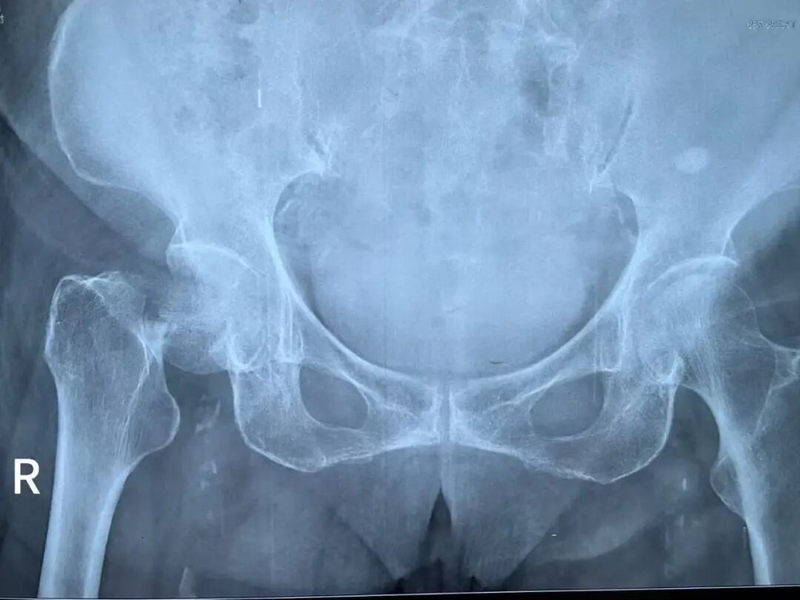

1月15日晚9点,青岛西海岸第二医院关节外科单彬副主任接诊了一位因在家中摔倒导致右髋关节疼痛伴活动受限的86岁高龄患者。经诊断,患者为右侧股骨颈骨折—这是老年群体中被称为“人生最后一次骨折”的高危损伤,常因各种并发症危及生命。

关节外科单彬主治医师提前定制围手术期快速康复(ERAS)管理方案,优化术前、术中和术后处理措施,实现快速康复、缩短住院时间、降低并发症发生率和再入院风险;并结合影像学检查(术前影像显示股骨颈移位明显),联合李阳副主任医师共同制定手术方案,确定实施右髋人工股骨头置换术,以最小创伤实现快速康复。麻醉科全面评估老人心肺功能,量身定制个体化麻醉方案,通过精准用药提前控制血压、血糖及心律失常,将麻醉风险降到最低;心内科全程深度参与,指导围手术期心血管用药,积极转复心律,实时监测心脏功能,为手术期间的循环稳定保驾护航。